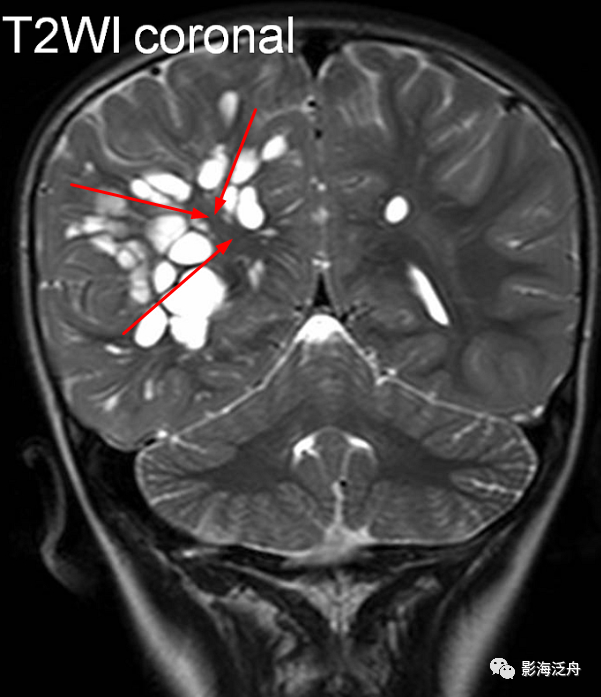

vr腔隙,腔梗灶,微出血,脱髓鞘,傻傻分不清?快看这里!

图片尺寸601x697